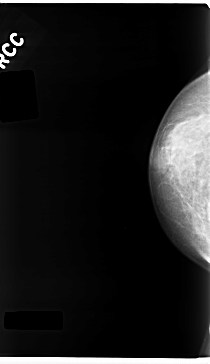

Digital Database for Screening Mammography

Volume: benign_01 Case: C-0237-1

C_0237_1.RIGHT_CC

ics_version 1.0

filename C-0237-1

DATE_OF_STUDY 19 8 1994

PATIENT_AGE 62

FILM_TYPE REGULAR

DENSITY 3

DATE_DIGITIZED 28 4 1998

DIGITIZER LUMISYS LASER

RIGHT_CC LINES 4720 PIXELS_PER_LINE 2720 BITS_PER_PIXEL 12 RESOLUTION 50 NON_OVERLAY